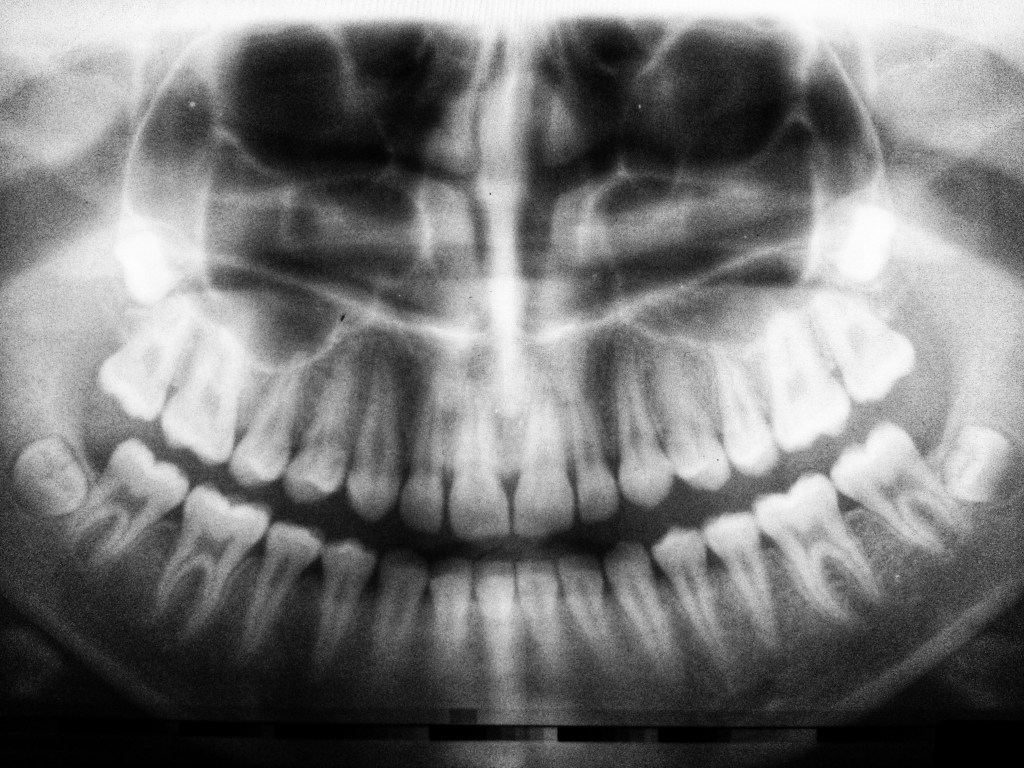

Encrusted on my canines

Are names of men and women

My molar teeth stained from knowing

and the gaps between

Plugged with phantom rotten flesh.